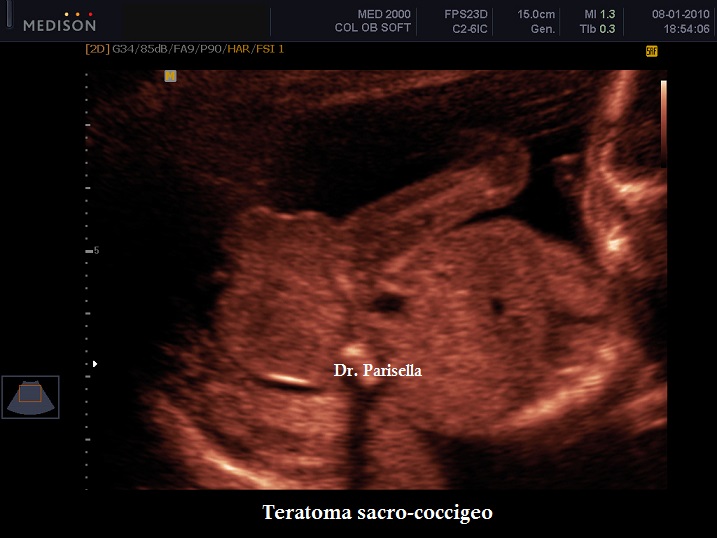

Dal punto di vista ecografico si presenta come una massa esofitica ad origine dalla regione sacrale, ad aspetto di tipo solido o complex nell'85% dei casi o di tipo cistico nel 15% dei casi; nel 35% dei casi sono presenti delle calcificazioni.

Il teratoma sacro-coccigeo viene classificato in quattro tipi (Altman 1974) in rapporto alla localizzazione del tessuto tumorale all'interno o all'esterno della pelvi.

• Tipo I   : tumore prevalentemente esterno

• Tipo II  : tumore con componente esterna ed intrapelvica sovrapponibili